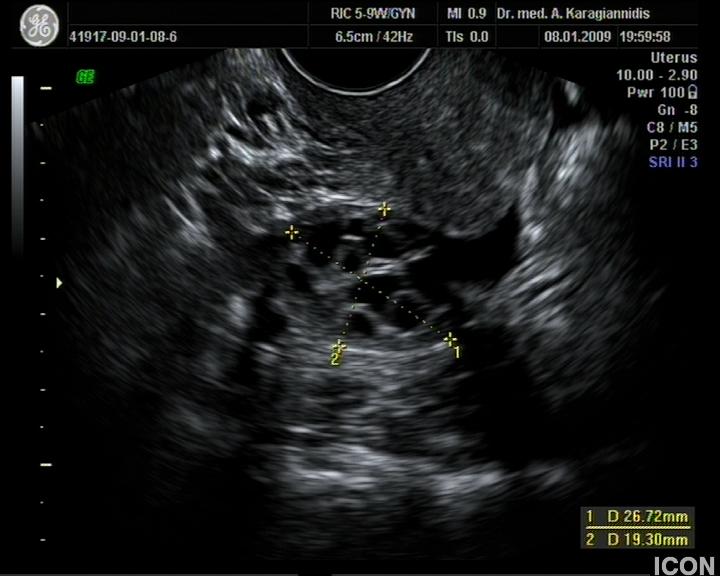

Αυχενική διαφάνεια

Η αυχενική διαφάνεια (ΑΔ) είναι η συλλογή υγρού στον τράχηλο του εμβρύου και συγκεκριμένα ανάμεσα στο δέρμα και στους ιστούς που καλύπτουν τη σπονδυλική στήλη.